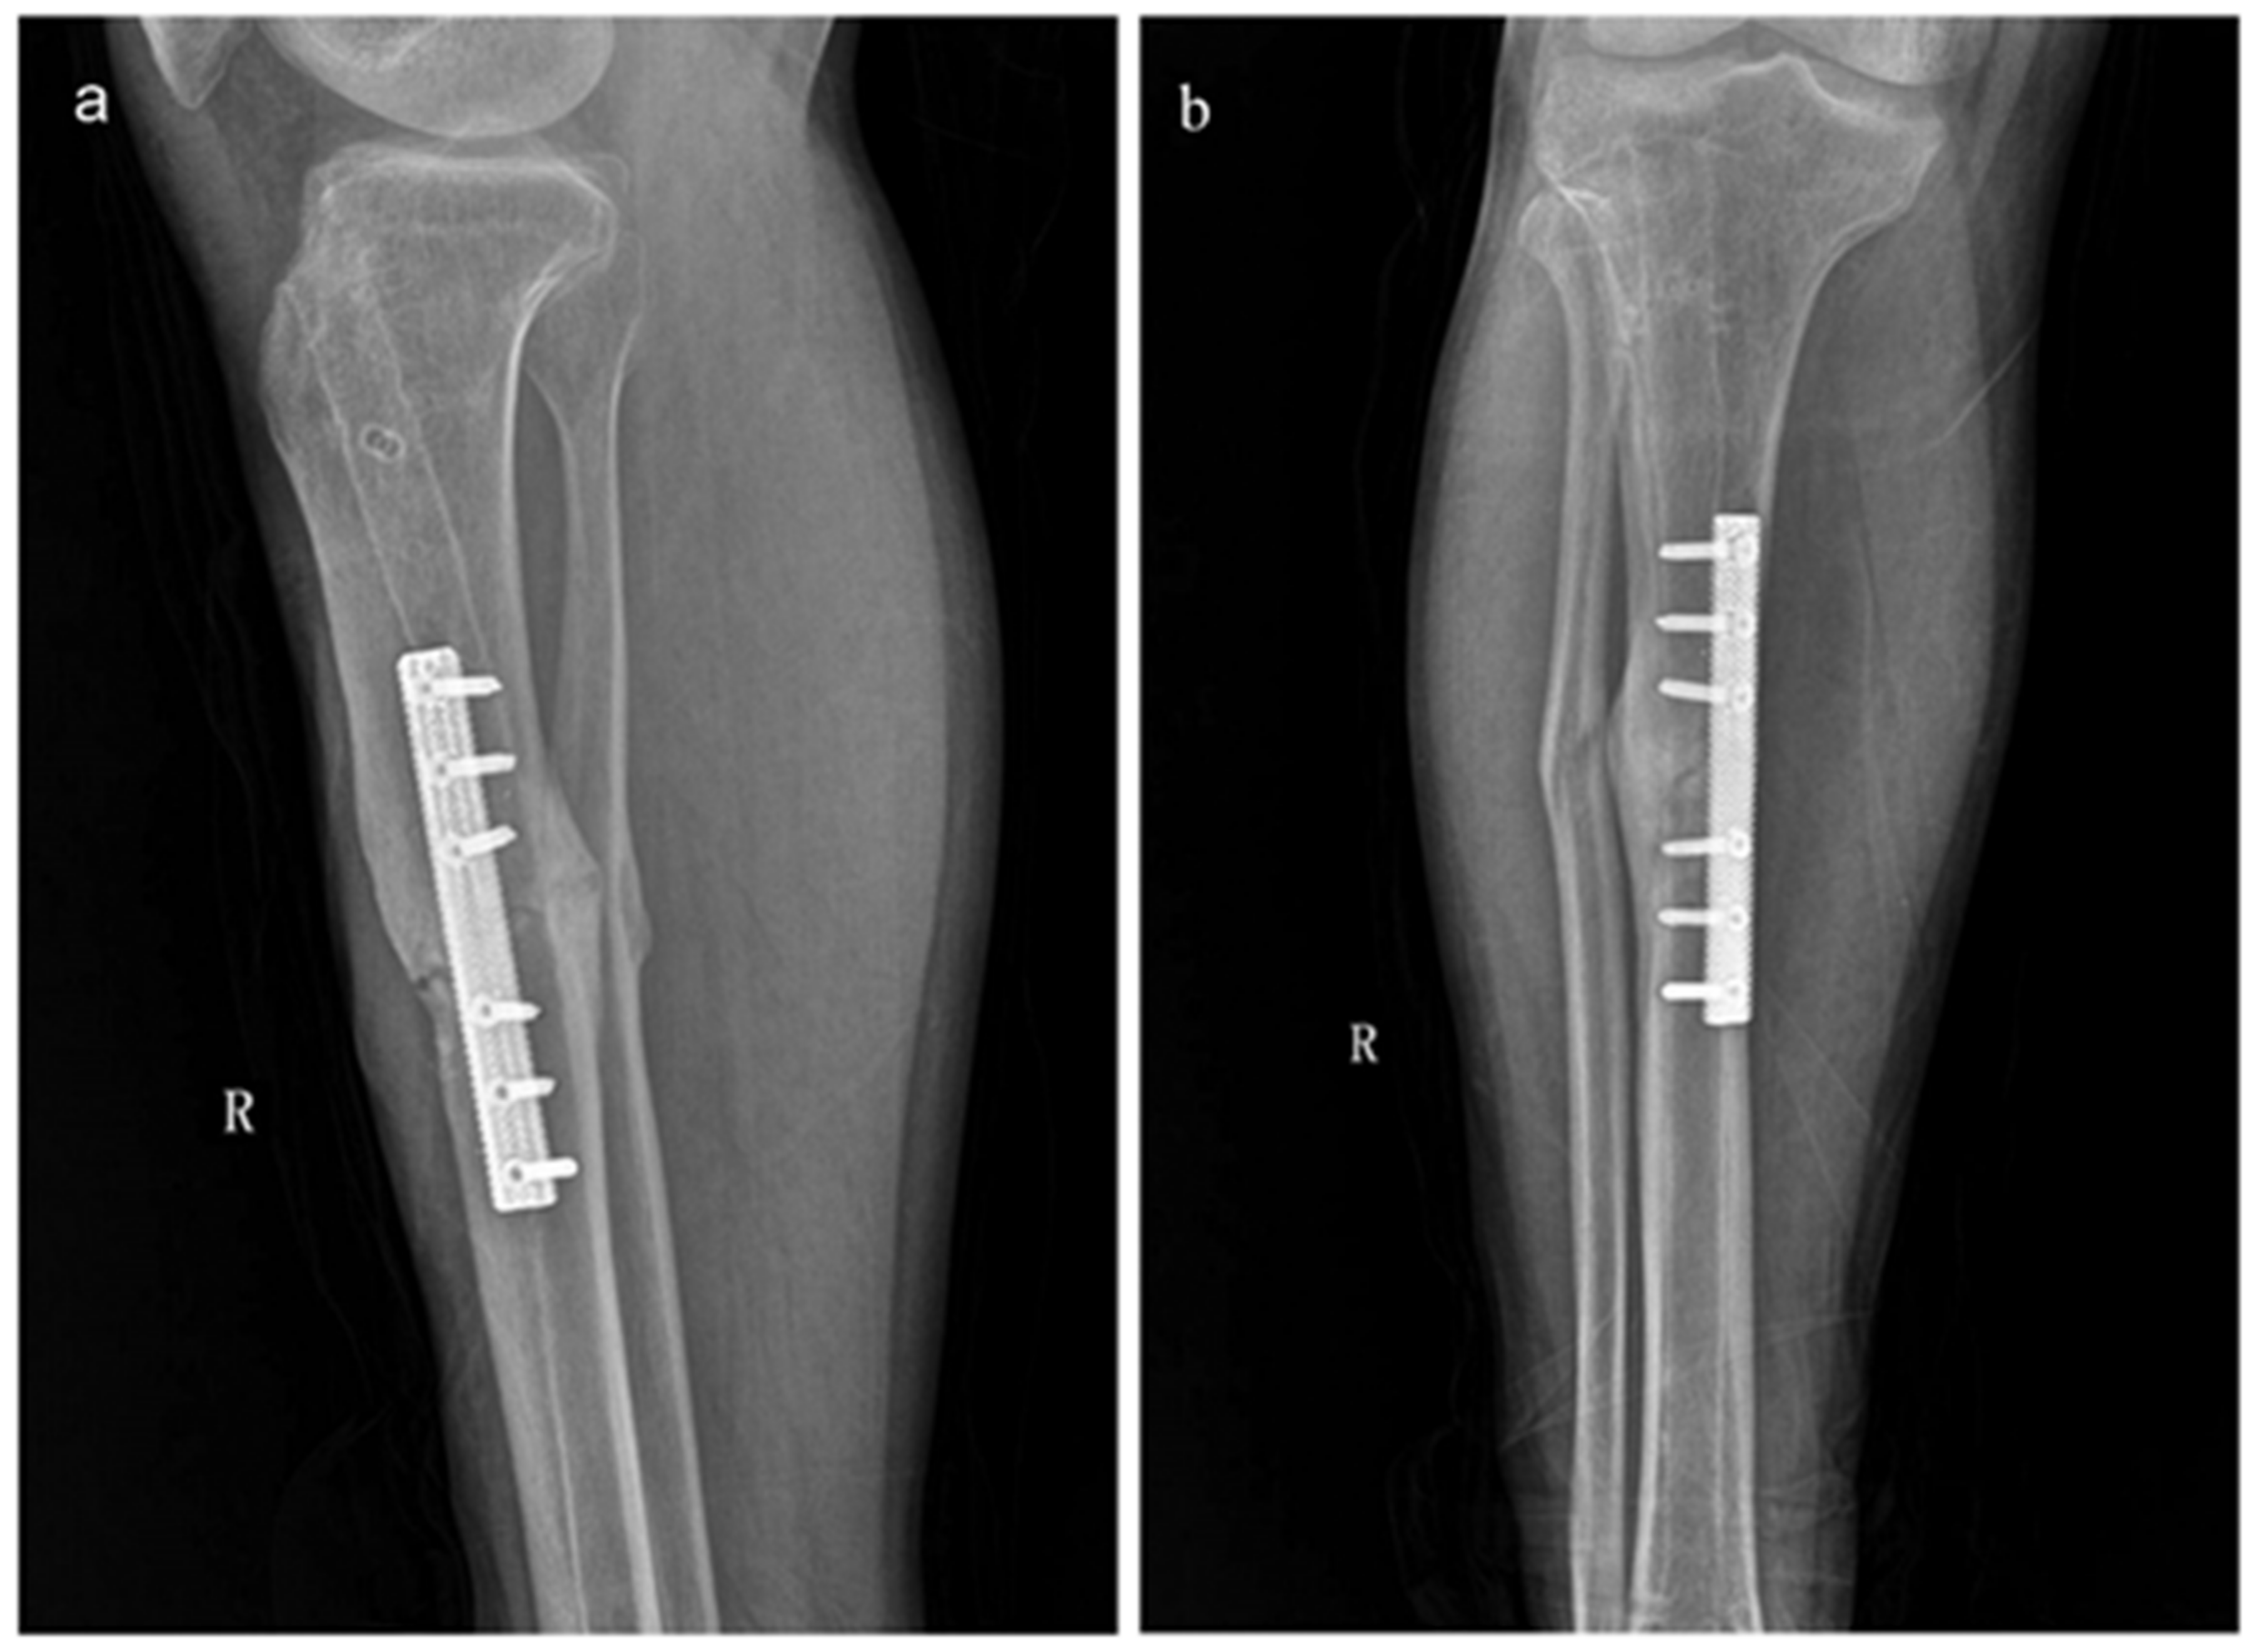

A printed porous Ta osteosynthesis plate has been used for the treatment of a 30-year old male patient with tibial nonunion [191]. The patient had undergone intramedullary nail fixation three times previously, but failed to attain healing even associated with the iliac crest autograft. Owing to its biological and biomechanical advantages, this novel porous Ta plate (80% porosity, 1.5–10 GPa elastic modulus) reunited the tibial shaft fracture uneventfully 5 months after the fourth surgery, and the patient regained normal mobility (Figure 6).